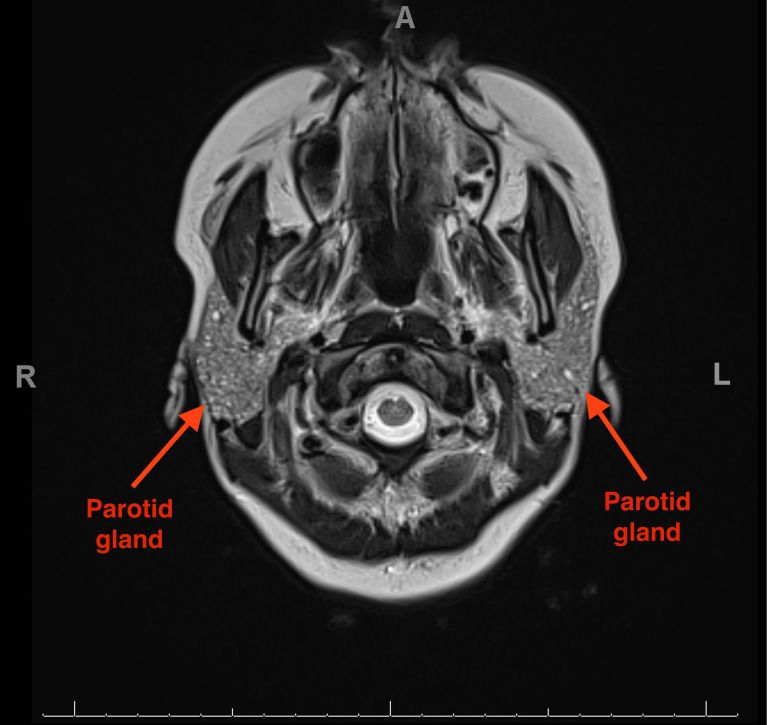

Salt and Pepper Parotid Changes in Sjögren's Syndrome.

盐和胡椒在Sjögren综合征中的腮腺变化。